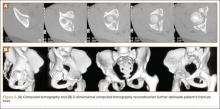

Immediate postoperative radiographs were evaluated by 3 orthopedic surgeons blinded to the patients’ clinical outcomes. Displacement was evaluated on anteroposterior (AP) and Judet views of the pelvis, as described by Matta,22 and reductions were classified as anatomical (0-1 mm of displacement), imperfect (>1 to 3 mm), poor (>3 mm), or surgical secondary congruence (Table 2).

Thirty-seven patients underwent acetabular fracture ORIF. Immediate postoperative radiographs showed 30 anatomical reductions and 7 imperfect reductions. One patient had surgical secondary congruence and developed AVN of the hip. We could not identify an association between the quality of the reduction and the outcome with respect to pain or return to activity. However, no patient had a poor reduction. An illustrative case is presented in Figures 1 to 4.